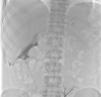

Ours was a 47 year-old patient with chronic renal failure from interstitial nephropathy secondary to reflux, who had been on haemodialysis since 1990. He underwent his first kidney transplant in 1991, which was then removed due to chronic dysfunction, and underwent a second transplant in 1999, which was again lost to the same reasons. He returned to haemodialysis in 2010. Due to intolerance to the second kidney, the patient underwent graft embolisation. He was receiving lanthanum carbonate at 750mg/8 hours due to secondary hyperparathyroidism and hyperphosphataemia. Due to several failed vascular accesses, it was suggested that the patient be transferred to peritoneal dialysis, and a straight, double-cuff Tenckhoff catheter was implanted. During training, we detected catheter malfunction with incomplete drainage, so we performed abdominal x-rays (Figure 1) and peritoneography (Figure 2). In addition to the remnants of the radio-opaque material from the graft embolisation, we observed a large quantity of faecal matter throughout the large intestine, with radiolucent images indicating the presence of lanthanum carbonate. The peritoneal catheter was poorly positioned towards the hepatic flexure of the colon, and the peritoneography dye was completely restricted between the transverse colon and the lower edge of the liver, which was clearly outlined, without disseminating into the rest of the abdominal cavity. Suspension of the lanthanum and intensive laxative treatment progressively resolved the constipation and dye restriction, although it did not resolve the poor positioning of the catheter, which had to be relocated.

Figure 1. Simple abdominal x-ray